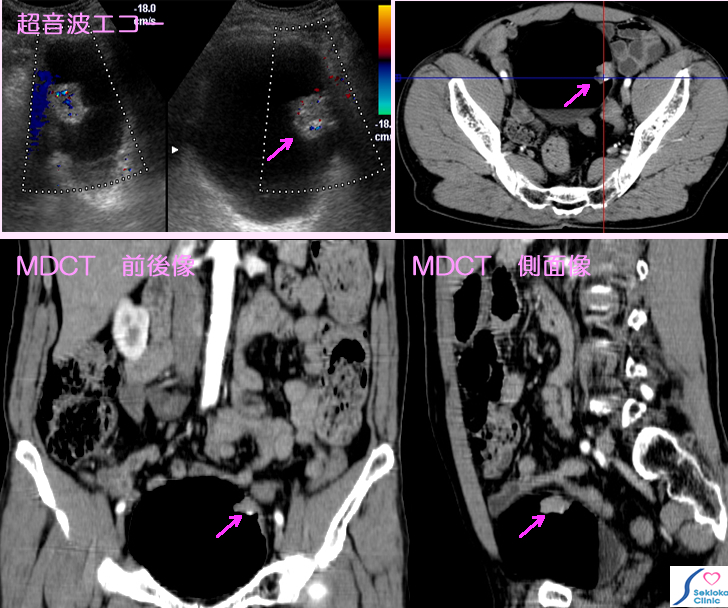

膀胱がん診断画像

膀胱早期がん

自覚症状  血尿(赤い尿)に気づき来院

超音波エコー検査で膀胱内膜から突出する小腫瘍認め、

造影MDCT検査行う。膀胱壁外への進展の所見認めず、

早期がん と推定される

治療  早期がんであったため、経尿道的切除で膀胱は温存される